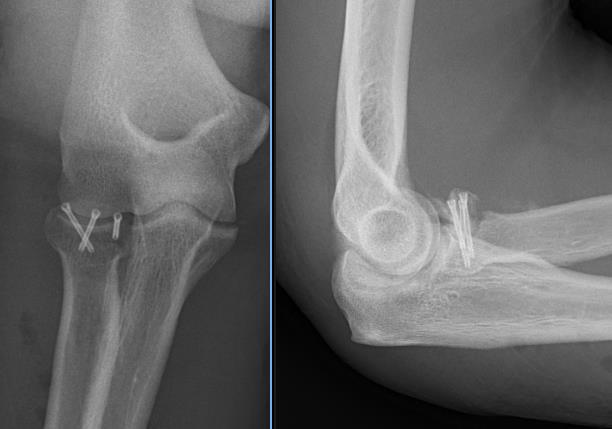

Radial Head Arthroplasty (RHA)

Design

Cobalt chrome / pyrocarbon / titanium

Modular - various head diameter / thickness + various stem sizes + collars to build up radial neck if required

Fixation - press fit v loose fit

Technique Modular Titanium Radial Head Arthroplasty

Overstuffing

| Lesser sigmoid notch | Symmetry of ulnohumeral joint |

|---|---|

|

Radial head shoulder articulate with lesser notch

Ensure no gapping of lateral ulnohumeral joint |

- cadaveric study

- increased medial ulno-humeral joint line gapping with overlengthening of 6 or 8 mm

- increased lateral ulno-humeral joint line gapping with overlengthening of 2 mm